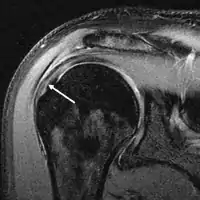

MRI

Magnetic resonance imaging (MRI) and ultrasound[42] are comparable in efficacy and helpful in diagnosis although both have a false positive rate of 15–20%.[43] MRI can reliably detect most full-thickness tears although very small pinpoint tears may be missed. In such situations, an MRI combined with an injection of contrast material, an MR-arthrogram, may help to confirm the diagnosis. It should be realized that a normal MRI cannot fully rule out a small tear (a false negative) while partial-thickness tears are not as reliably detected.[44] While MRI is sensitive in identifying tendon degeneration (tendinopathy), it may not reliably distinguish between a degenerative tendon and a partially torn tendon. Again, magnetic resonance arthrography can improve the differentiation.[44] An overall sensitivity of 91% (9% false negative rate) has been reported indicating that magnetic resonance arthrography is reliable in the detection of partial-thickness rotator cuff tears.[44] However, its routine use is not advised, since it involves entering the joint with a needle with potential risk of infection. Consequently, the test is reserved for cases in which the diagnosis remains unclear.